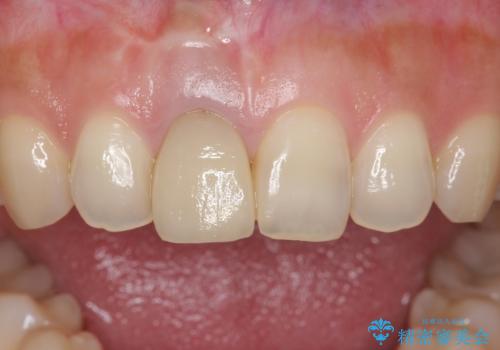

- もっと自然にみえるような差し歯にしたいと希望され来院された患者様です。

患者様の天然歯はグラデーションがあり切縁(歯冠の先端)はやや透けていて透明感があるのに対し、前歯(右上1)の差し歯はやや黄色く不透明で単調な色味でした。

患者様のご希望により、右上1はジルコニアクラウン(スペシャル)、右上5はジルコニアクラウン(スタンダード)へやりかえることにしました。

前歯のクラウンは一度修正し、患者様の理想とする色味や形態を追求しました。

天然歯と見紛うほどの自然な仕上がりに喜んで頂けました。

ジルコニアクラウンの繊細なグラデーション・透明感は熟練した技工士さんの技術の賜物です。

右上1:ジルコニアクラウン スペシャル

右上5:ジルコニアクラウン スタンダード